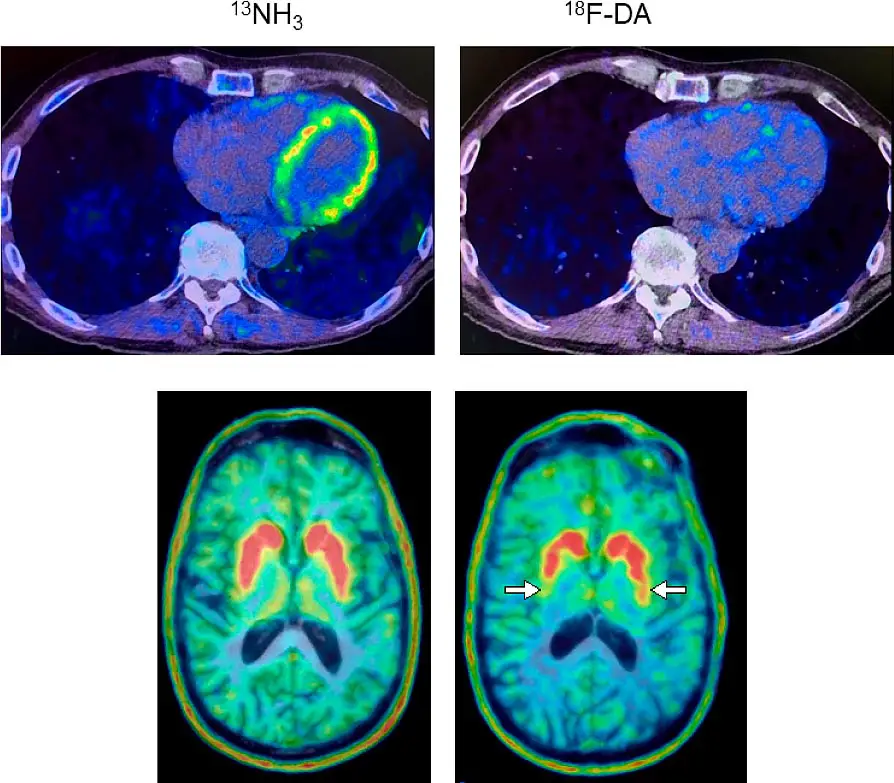

一位帕金森病患者的心脏和大脑 PET 扫描结果支持"身体先行"的发展过程。最上面的一对正电子发射计算机断层扫描图显示,心脏(右图)中的18F-多巴胺衍生放射性较低,而13N-氨正电子发射计算机断层扫描图(左图)则正常,这种情况发生在多巴胺生成神经元丧失和症状出现之前。图片来源:NINDS 戈德斯坦实验室

在本研究中,戈尔茨坦博士领导的研究小组发现,与具有相同风险因素但放射性正常的人相比,心脏中18F-多巴胺衍生放射性较低的高危人群在长期随访期间患帕金森氏症或路易体痴呆症的几率很高。PET 扫描通过使用放射性示踪剂来观察人体器官的代谢或生化过程。

研究人员对 34 名具有帕金森病风险因素的人进行了心脏 PET 扫描,以了解神经递质去甲肾上腺素的水平。他们发现,扫描结果可以区分出哪些人后来被诊断出患有帕金森病或路易体痴呆症--这两种疾病都是由于蛋白质α-突触核蛋白异常沉积形成被称为路易体的团块而引起的脑部疾病。这项研究是在美国国立卫生研究院临床中心进行的,该中心是目前进行 18F 多巴胺 PET 扫描的唯一地点。